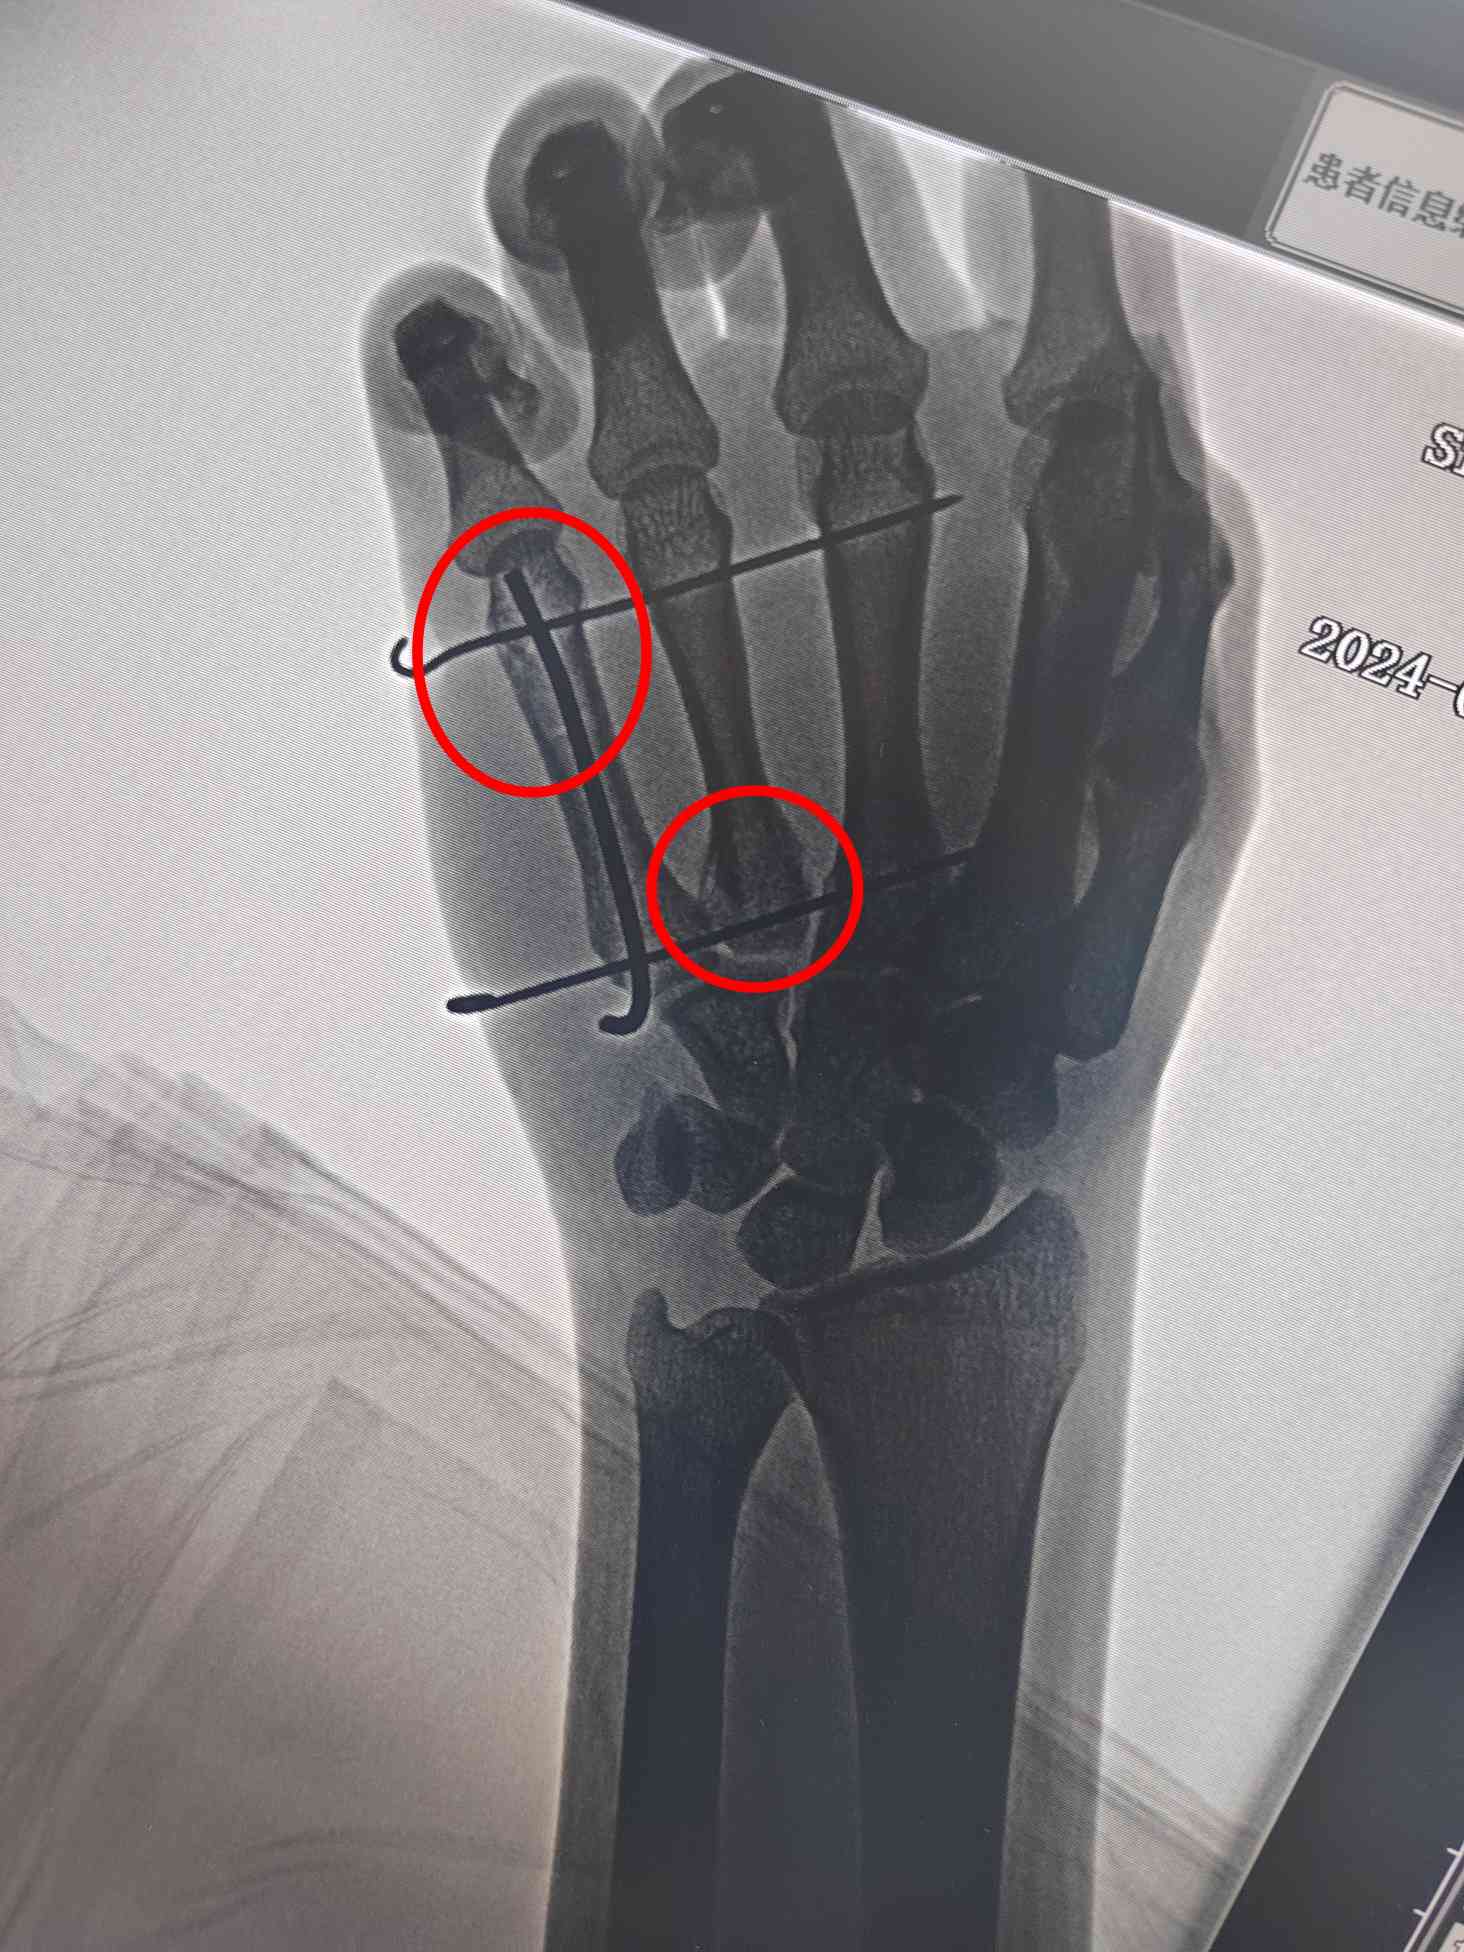

6月5日晚上8点,一家人带着最后的希望来到我院,找到了正在值班的薛继强医师。薛继强接诊这位特殊的患者后,立即汇报韩卢丽主任并商讨治疗方案。保守治疗需要石膏或支具外固定,这必然影响握笔写字,且骨折端的微动不利于消肿和缓解疼痛;切开复位钢板、螺钉内固定术虽然能够迅速稳定骨折端,但是切口长、创伤大,而且当前手术时机不成熟,此时小马的右手已经肿得像面包一样,切口感染风险较高;传统微创闭合穿针需要辅助石膏或支具外固定,同样影响握笔写字。有没有一种相对微创并且能够迅速稳定骨折端且不需要辅助外固定的治疗方法呢?经过科内讨论,同时参考国内同行的建议,薛继强建议急诊行“微创闭合复位髓内穿针结合克氏针支架固定术”。抽血、化验、心电图、胸片,迅速完善术前检查,与患者及家长沟通,术前谈话、签字,患者入院后3小时——晚上11点,患者进入手术室,在手术医师、麻醉医师、巡回护士、影像技师的通力合作下,手术顺利完成,骨折达到了解剖复位的效果,稳定并加固了两处骨折部位,而且不需要石膏或支具外固定,达到了既稳定骨折端又不影响握笔写字的双重治疗目的。术后12小时,薛继强为小马换药的同时指导他握笔写字,术后14小时,小马便出院查看考场,术后32小时,小马顺利奔赴考场参加考试。高考结束后,通过电话回访,此次骨折并未给小马的考试造成太大的影响。

术后效果